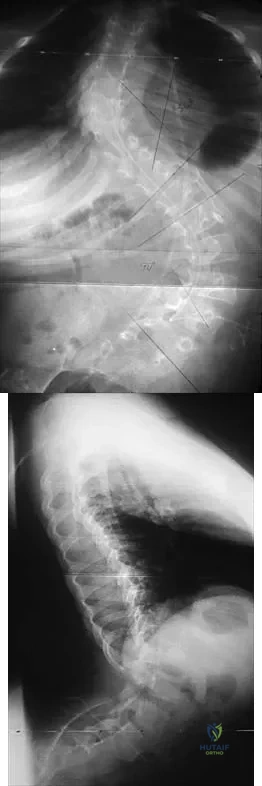

Question 963High Yield

The parents of a previously healthy 3-year-old child report that she refused to walk on awakening. Examination later in the day reveals that the patient can walk but with a noticeable limp. She has a temperature of 99.5 degrees F (37.5 degrees C). Range of motion measurements are shown in Figure 50. An AP pelvis radiograph is normal. Laboratory studies show a WBC count of 9,000/mm3 and an erythrocyte sedimentation rate of 10 mm/h. Management should consist of

Explanation

The patient has the typical history and presentation of transient synovitis of the hip, a condition that is more common in children age 2 to 5 years but which may affect children up to 12 years. The discomfort typically is noted on awakening, and the child will refuse to walk. Later in the day, the pain commonly improves and the child can walk but will have a limp. Mild to moderate restriction of hip abduction is the most sensitive range-of-motion restriction. The extent of the evaluation for transient synovitis depends on the intensity and duration of symptoms. Because she has been afebrile for the past 24 hours, observation is the management of choice. In the differential diagnosis of suspected transient synovitis, septic arthritis of the hip is the primary disorder to exclude. Osteomyelitis of the proximal femur also should be considered. In most patients, clinical examination will differentiate of these disorders to a reasonable certainty. Plain radiographs are normal in the early stage of an infectious process. Ultrasonography shows increased fluid in the hip joint in both transient synovitis and septic arthritis. MRI can differentiate the two conditions; however, this test would require general anesthesia and is not required in most patients in this age group. If a child with transient synovitis has a concurrent infectious process such as an upper respiratory tract infection or otitis media, the temperature will most likely be elevated. In this situation, a full evaluation for an infectious process and initiation of IV antibiotics should be considered. This would include radiographs, CBC count, erythrocyte sedimentation rate, blood cultures, aspiration of the hip joint, and IV antibiotics. Del Beccaro MA, Champoux AN, Bockers T, Mendelman PM: Septic arthritis versus transient synovitis of the hip: The value of screening laboratory tests. Annals Emerg Med 1992;21:1418-1422.